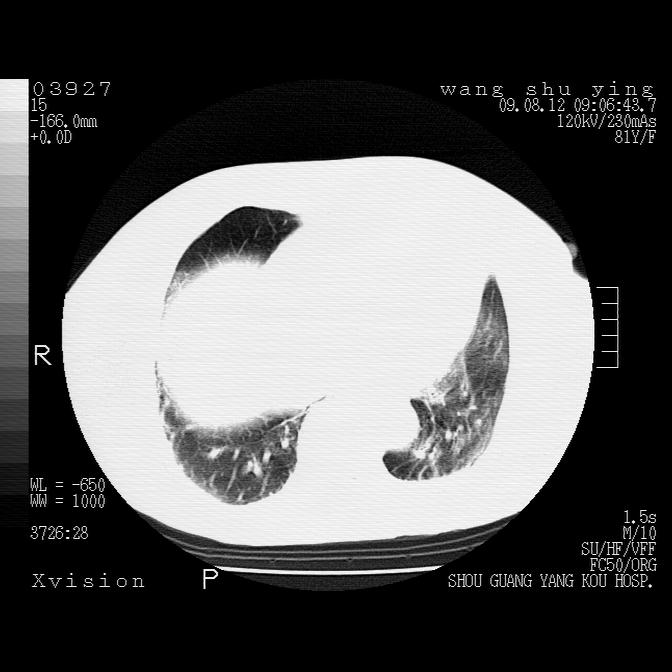

以下是引用帅河马在2009-8-12 12:59:00的发言:[br]两肺感染性病变伴双侧胸膜肥厚。[br]左侧甲状腺腺瘤不除外。[br]腹水+心包积液。[br][br][本贴已被 帅河马 于 2009-8-12 13:14:32 修改过]

以下是引用sdzyy在2009-8-12 18:17:00的发言:[br]两肺感染性病变伴双侧胸膜肥厚。[br]左侧甲状腺腺瘤不除外。[br]腹水+心包积液。[br]支持

以下是引用随光逐影在2009-8-12 19:42:00的发言:[br]1)两肺感染性病变伴双侧胸膜肥厚。2)不排除左侧甲状腺腺瘤。3)肝脏占位性病变;建议行进一步检查。